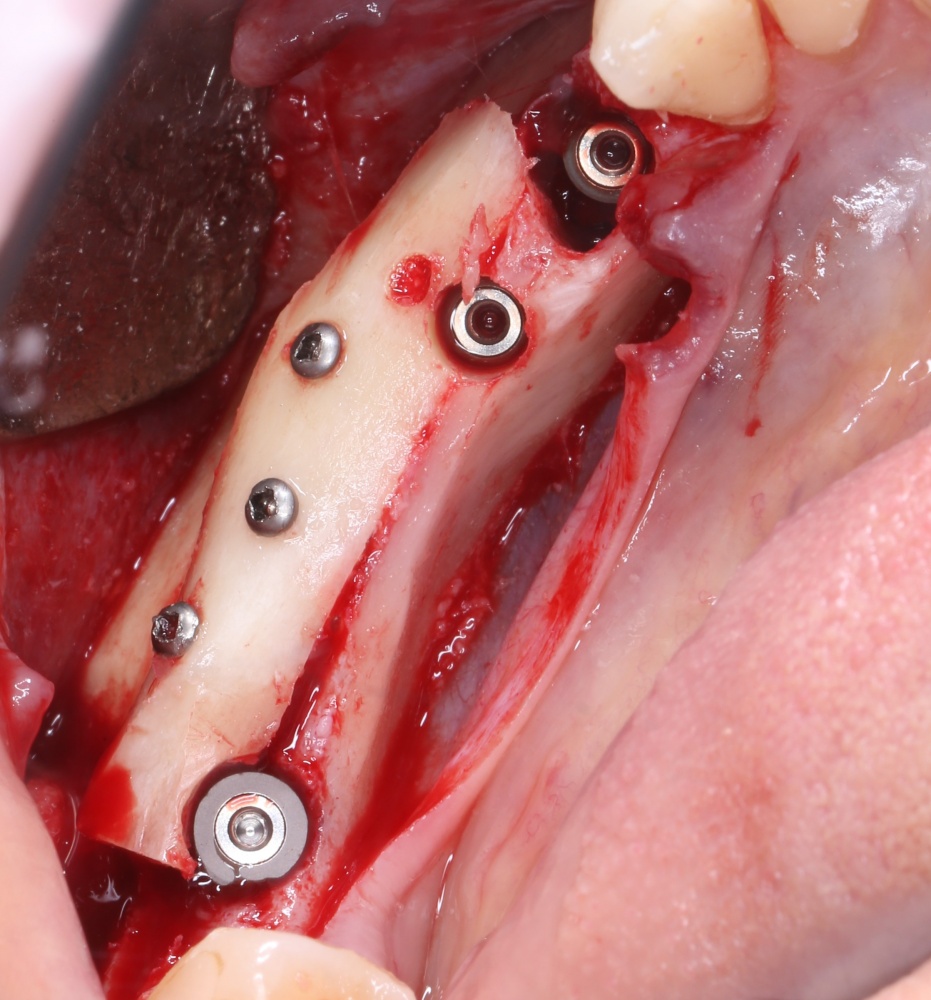

Рекомендации по установке имплантов. Для всех. Часть V.